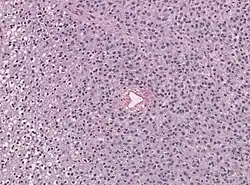

Mischgliome oder Oligoastrozytome sind diffuse Gliome des mittleren Erwachsenenalters, welche histologisch Oligodendrogliomen und Astrozytomen ähneln. Durch molekulargenetische Testungen können die Tumoren fast immer einem der beiden Typen zugewiesen werden. Seit der Revision der vierten Fassung der WHO-Klassifikation der Tumoren des zentralen Nervensystems von 2016 wird die Diagnose Oligoastrozytom, nicht näher bezeichnet nur noch dann empfohlen, wenn eine solche Testung nicht möglich ist.[1]

In Einzelfällen wurden auch Tumoren mit beiden Zelllinien molekulargenetisch nachgewiesen, diese können als dual-genotype oligoastrocytoma, not elsewhere classified (‚Oligoastrozytom mit doppeltem Genotyp, andernorts nicht klassifiziert‘) bezeichnet werden.[2]